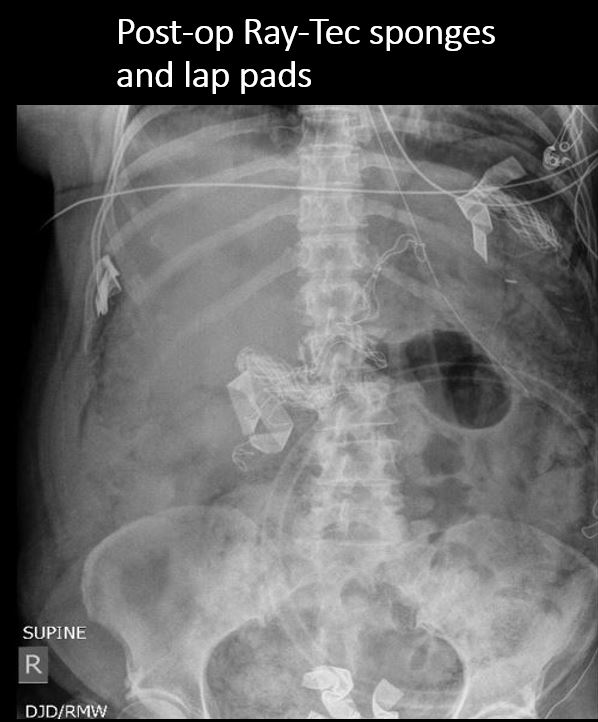

Section 1 Submit Findings CB1518 Findings Scout Image of the abdomen There is an NG/OG/FT tube which is malpositioned Yes No There is an unexpected radiopaque foreign body or incidental non-surgical foreign body in the abdomen or pelvis. Yes No There are additional lines, tubes, catheters or drains in place (examples include chest tubes, mediastinal drains, rectal temperature probe, etc.). Yes No There is dilatation with gas or fluid of multiple or diffuse loops of bowel. Yes No ​Both the small and large bowel are filled with air and/or fluid and may or may not be distended. Yes No There is a paucity of gas in the abdomen. Yes No There are centralized loops of small bowel with distention of the abdomen and pelvis. Yes No There is organomegaly. Yes No There are intra-abdominal calcifications. Yes No There is free air present. Yes No The visualized bones are abnormal. Yes No Fluoroscopic examination of the chest shows pneumonia, atelectasis, or cardiomegaly. Yes No The hemidiaphragmatic excursions are inequal and nonsynchronous. Yes No Procedural The patient was given thin barium/water soluble contrast to drink via bottle/syringe/sippy cup/straw/cup. A total of---mL of thin barium/water soluble was used for this examination. Yes No The exam is limited by patient motion or non-cooperativity. Yes No The exam is limited by small or inadequate boluses/contrast intake. Yes No The swallowing act is abnormal. Yes No There is tracheal aspiration. Yes No The course of the esophagus is abnormal. Yes No The caliber of the esophagus is abnormal. Yes No There is stenosis of the upper/mid/distal esophagus. Yes No There is dilatation of the upper/mid/distal esophagus. Yes No There is a tracheoesophageal fistula present. Yes No There is a filling defect. Yes No There is dysmotility of the esophagus. Yes No There is extrinsic mass effect. Yes No There is a vascular ring. Yes No The stomach does not fill readily. Yes No If the contrast is instilled via NG tube/gastrostomy tube/orogastric tube: There is abnormal contrast opacification of the stomach. Yes No The stomach empties abnormally. Yes No There is gastric outlet obstruction. Yes No The duodenal C-loop is abnormal in size. Yes No The location of the ligament of Treitz is abnormal. Yes No The proximal jejunum is dilated. Yes No There is gastroesophageal reflux observed to the upper/mid/distal esophagus. Yes No The reflux does not clear quickly. Yes No N/A